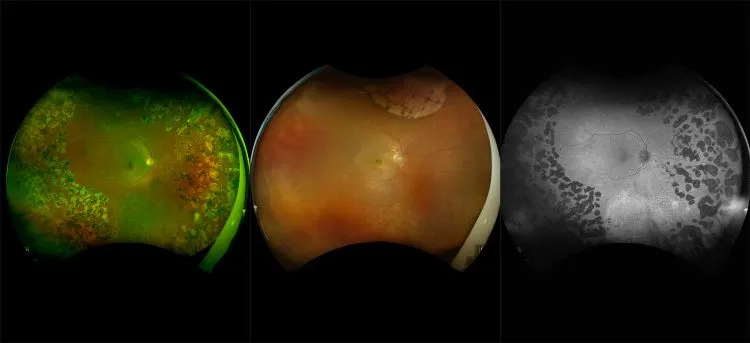

optomap Multimodal Diabetic Eye Disease Cases

Optos offers multimodal imaging with all ultra-widefield devices. Having both ultra-widefield and four images captured in less than one second has been shown to enhance pathology detection and disease management as well as improve practice and clinic flow. Ultra-widefield multimodal imaging is important across all access points of patient care - screening, detection, diagnosis, and treatment.